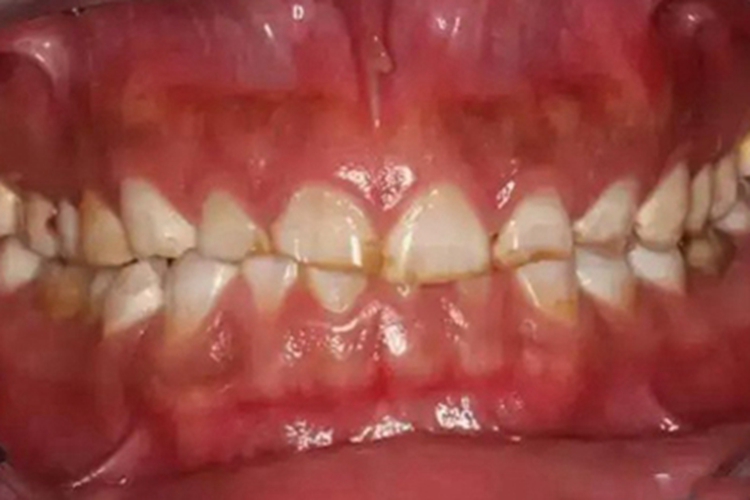

酸蚀症发生后,可见患者骨质被腐蚀破坏,局部缺损,部分牙齿前半段几乎消失而变短,缺损边缘处发黄褐色。患者外在形象因此受影响,容易出现自卑、抑郁等负面情绪。

酸蚀症牙齿缺损变短,是牙齿长期受到非细菌性酸的作用而发生脱矿,表面缺损的表现。患者有喜食酸性饮料、食物,长期接触酸雾或胃病反酸的历史。